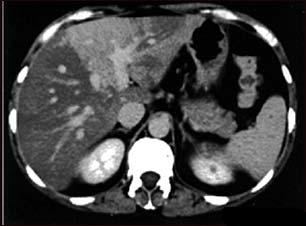

Steatohepatita nonalcoolica (NASH)